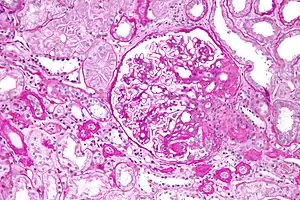

On histology, FSGS manifests as damage (sclerosis) to segments of glomeruli; moreover, only a portion of glomeruli are affected.[19][20] The focal and segmental nature of disease seen on histology help to distinguish FSGS from other types of glomerular sclerosis.[20]

Diagnosis of FSGS is made by renal biopsy that includes at least 15 serial cuts with at least 8 glomeruli.[30][31] Histologic features include sclerosis (scarring) of a portion (average: 15%) of the glomerular space, with only a portion of glomeruli manifesting any sclerosis.[31]

Five mutually exclusive variants of focal segmental glomerulosclerosis may be distinguished by the pathologic findings seen on renal biopsy:[32]

Recognition of these variants may have prognostic value in individuals with primary focal segmental glomerulosclerosis. The collapsing variant is associated with higher rate of progression to end-stage renal disease, whereas the glomerular tip lesion variant has a low rate of progression to end-stage renal disease in most patients.[8] The cellular variant shows similar clinical presentation to collapsing and glomerular tip variant but has intermediate outcomes between the other two variants.[8]